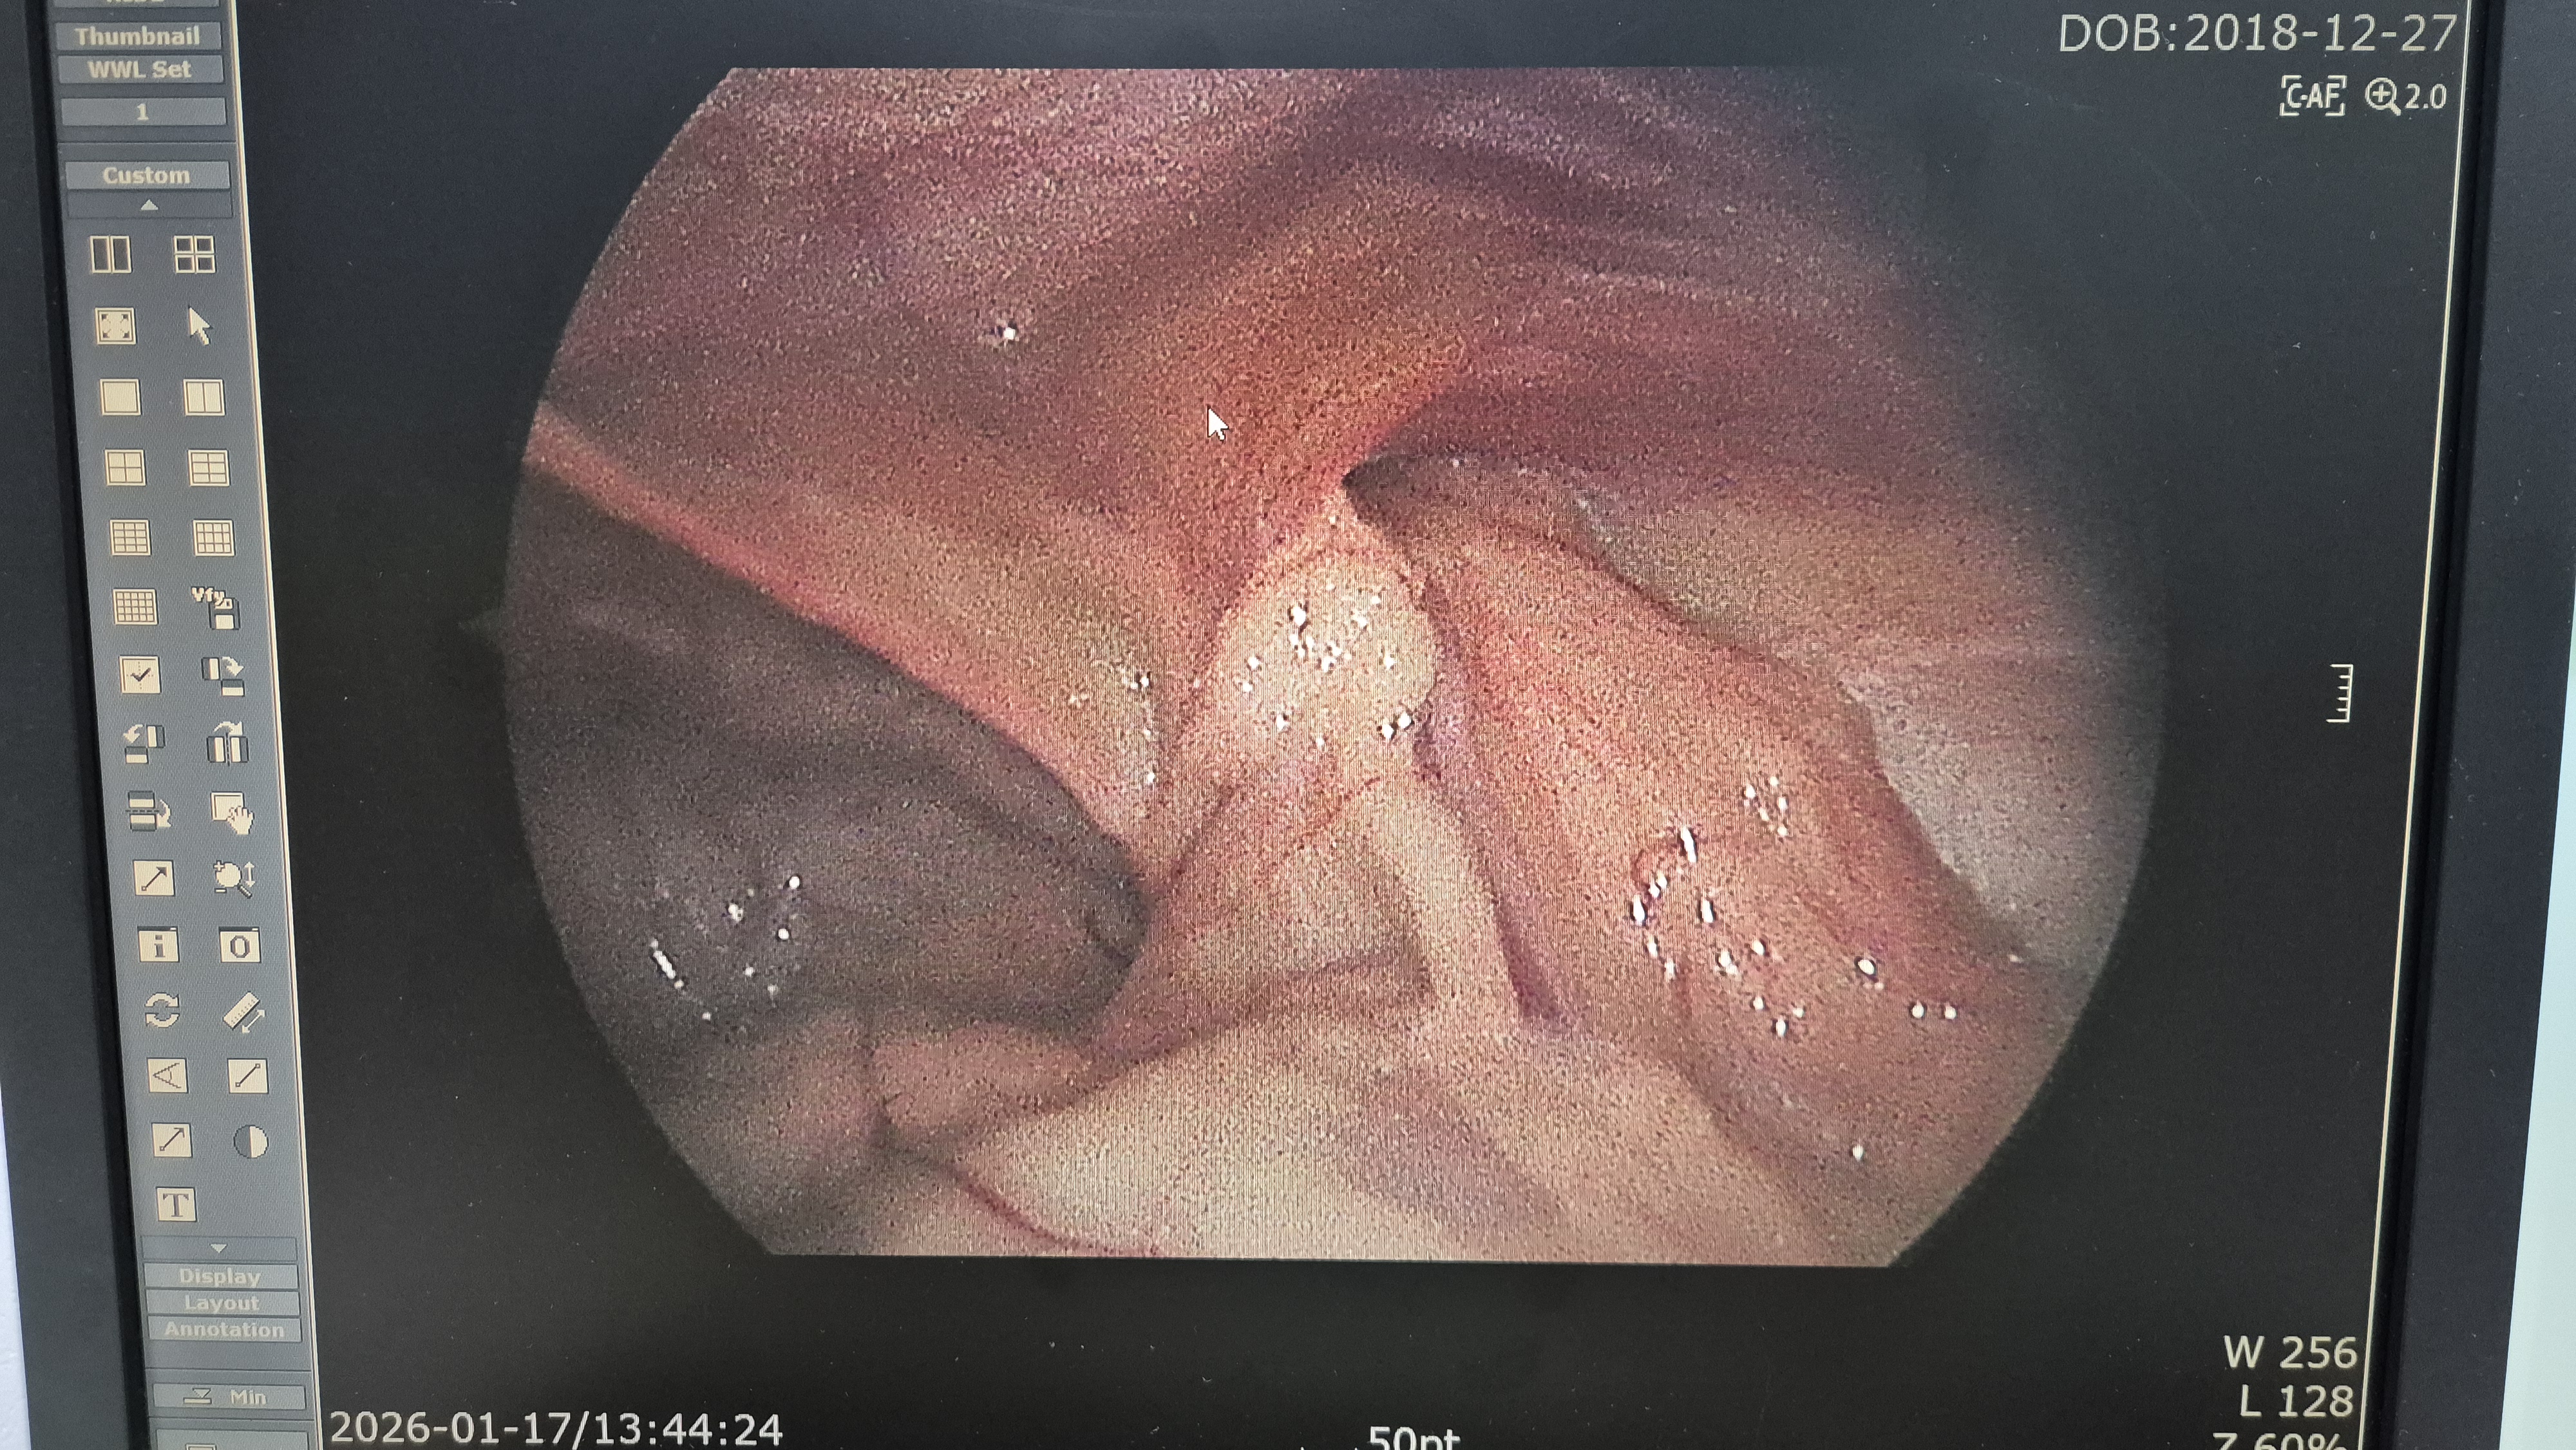

탈장과 감돈된 대망 확인.